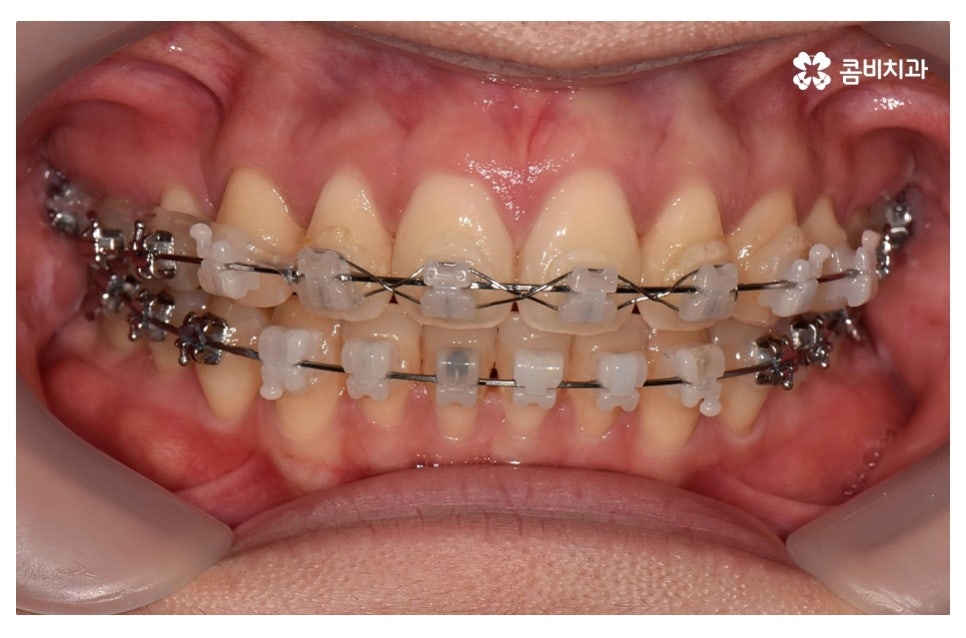

이번 포스팅에서 보인 덧니교정 사례의 경우 기능이 적은 작은 어금니를

발치하여 교정이 진행되었으며 발치를 진행하는 경우

작은 어금니를 발치하는데 충치 등으로 인해 손상이 큰 치아를

발치하는 경우가 일반적이라고 할 수 있어요.

요즘은 교정 장치의 선택에 있어서 다양한 선택이 가능하지만

보편적으로는 본 포스팅의 사례처럼 클리피씨 교정이 많이 선호되고 있어요.

클리피씨 교정은 일반적인 교정보다 치료 기간을 단축시킬 수 있고

통증이 비교적 적으며 세라믹 재질로 심미적이라는 장점이 있어요.

위 환자분의 경우 덧니교정에 걸린 치료 기간은 약 24개월 정도이며

성인 이후에 치료를 진행한 사례라고 볼 수 있어요.